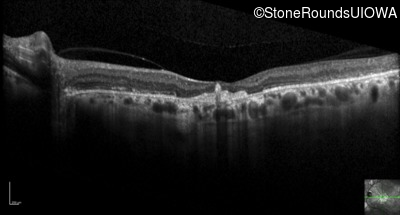

Optical Coherence Tomography - Right - 20/80

Exemplar / OCT Stack

OCT Stack